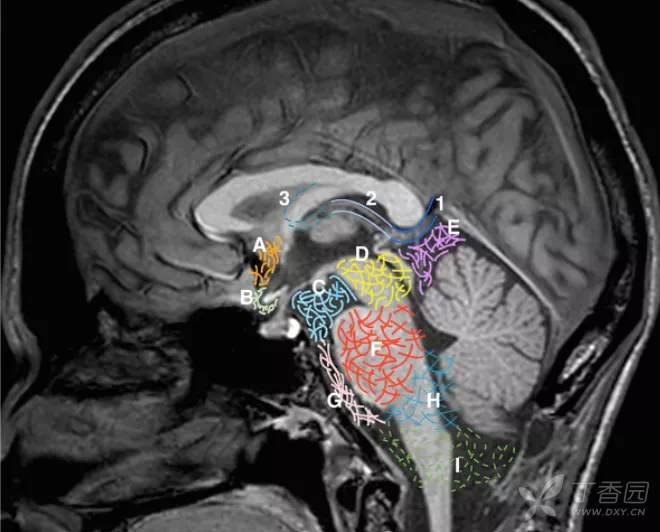

大脑大静脉池

大脑大静脉池 Galen's vein cistern 是四叠体池向上的延续,居第三脑室的后方,上抵胼胝体压部。池内前有松果体,后有大脑大静脉。

1. Great cerebral vein of Galen. 2. Internal cerebral vein. 3. Thalamostriate vein. A. Cistern of the laminae terminalis. B. Chiasmatic cistern. C. Interpeduncular cistern. D. Ambient cistern. E. Quadrigeminal cistern. F. Cerebellopontine cistern. G. Prepontine cistern. H. Lateral cerebellomedullary cistern. I. Cisterna

在CT 图像上,大脑大静脉池在第三脑室上部与“V” 型小脑幕影之间,与第三脑室上部共同显示为菱形低密度区。池内的松果体易于显影,如钙化则更为明显,而大脑大静脉须强化后才能看到。